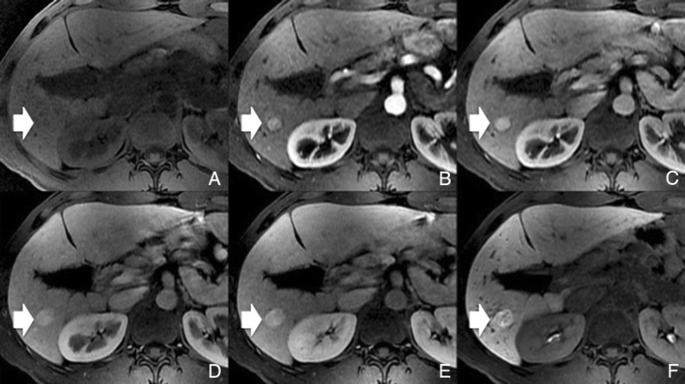

Методы динамического контрастирования печени на МРТ

Раздел: Снимки-подсказки